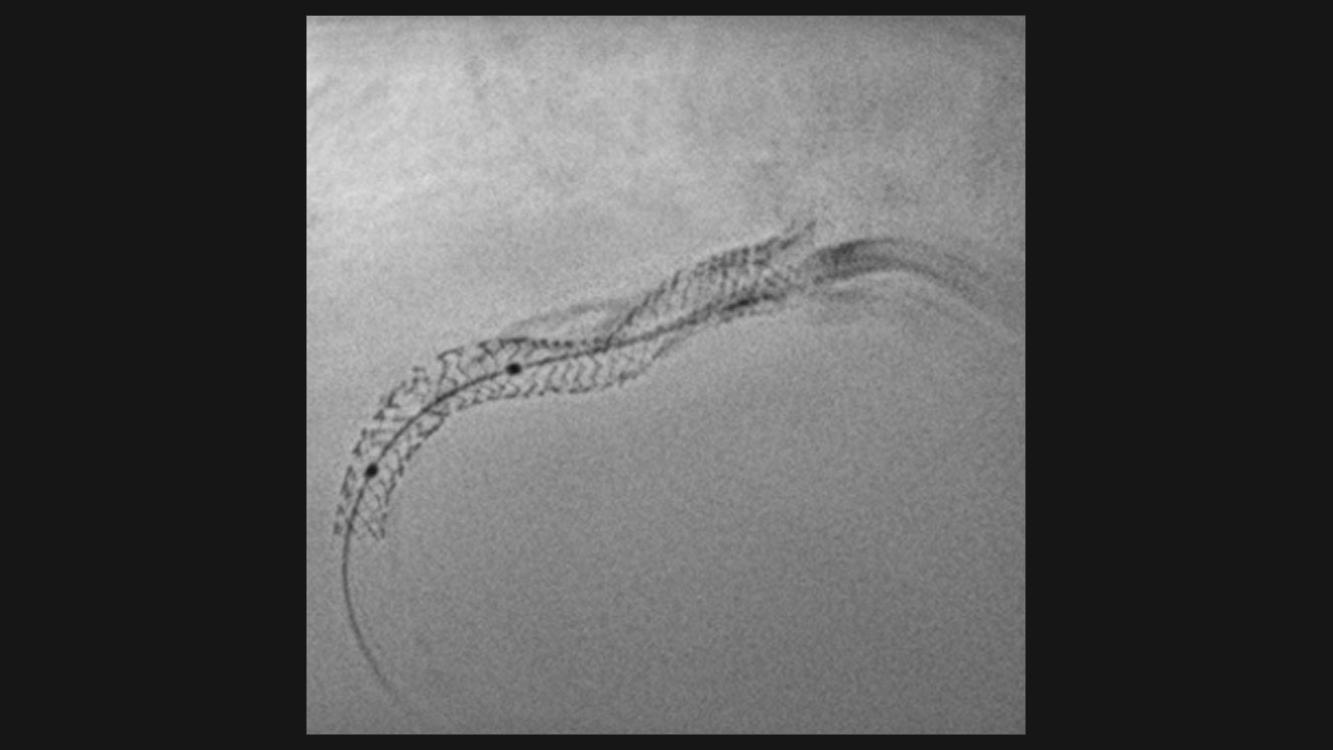

Precise system movements

Precision is key to improve the workflow in complex procedures. The reuse of vessel maps for DSA and 3D Roadmap even after C-arm and table movements speeds up the intervention and reduces dose and use of contrast media. ARTIS icono supports this with a (re)positioning accuracy of better than 0.5 mm.